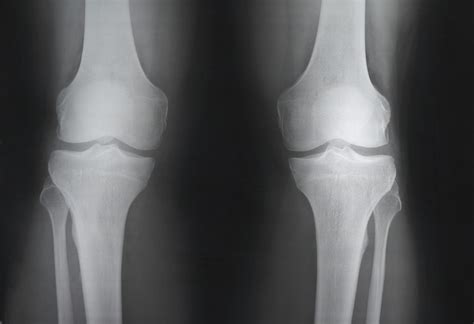

When you experience persistent knee pain, stiffness, or after a sudden injury, your primary care physician or orthopedist will often recommend imaging studies to determine the root cause. One of the first diagnostic tools utilized in clinical practice is a normal knee xray. While the term "normal" might sound dismissive if you are currently in pain, in the world of radiology, it is a crucial piece of information. It signifies that your bone structure, alignment, and joint space do not show immediate signs of fracture, severe dislocation, or advanced degenerative disease. Understanding what this medical imaging report actually means can help you navigate your treatment plan more effectively.

Because X-rays primarily capture dense tissue, a "normal" result confirms that the structural framework of your knee is intact. This is excellent news if you were concerned about a broken bone or severe bone deformity.

Receiving a normal knee xray result is actually a productive step in the diagnostic process. It allows your healthcare provider to rule out high-acuity bone issues like fractures or bone tumors. Once these are eliminated, your doctor can focus on a functional assessment. This often involves: